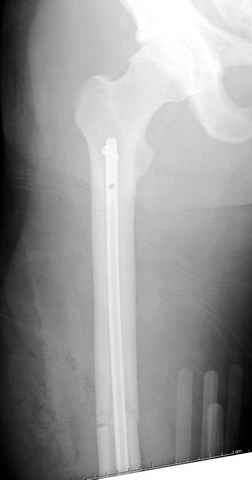

По поводу открытого перелома больной ургентно взят на ретроградное интрамедулярное штифтование, после рутинного дебрайдмента и фасциотомии на бедре и на голени.

перелом бедра

постоперационные